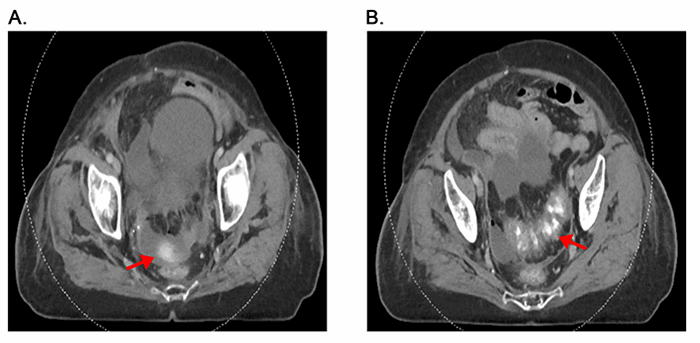

Six weeks later, the patient presented to the hospital with acute worsening of abdominal pain and hematochezia. On physical examination, she was febrile with a temperature of 39.2°C, hemodynamically normal, and had significant abdominal tenderness. Pertinent laboratory values included a white blood cell count of 19,600 cells/μL, hemoglobin of 8.6 g/dL, creatinine of 0.84 mg/dL and lactate of 0.8 mmol/L. She was given two units of blood, intravenous fluids and empiric antibiotics. Abdominal and pelvic CT evaluation with PO and IV contrast showed free air in the abdomen and complex ascites with extraluminal contrast, consistent with bowel perforation of the sigmoid colon. Marked thickening of the descending and rectosigmoid colon with pericolonic stranding was also identified (Figure 1). The decision was made to take her to the operating room for exploratory laparotomy.

Figure 1. Pre-operative CT imaging. A. Complex free fluid with evidence of extraluminal contrast (red arrow), consistent with bowel perforation.B. Sigmoid colonic thickening (red arrow) with pericolonic fat stranding and complex pelvic ascites.